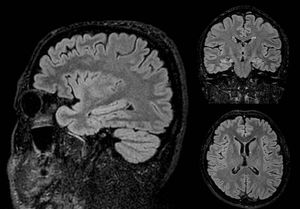

CUBE/SPACE/VISTA are 3D fast/turbo spin echo (FSE/TSE) sequences optimized for half Fourier parallel imaging with long echo trains, low flip angles and low specific absorption rates (SAR). Figure Isotropic T2-FLAIR-CUBE brain images.